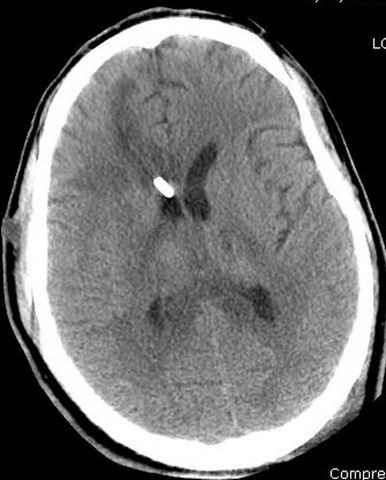

03.14.2005

больному 42, автоавария, политравма, открытая черепномозговая травма, безсознании, открытый перелом бедра, размозжение мягких тканей, дефект кожи на передней поверхности бедра около 13 см2 от ожога, компартмент синдром.

По поводу открытого перелома больной ургентно взят на ретроградное интрамедулярное штифтование, после рутинного дебрайдмента и фасциотомии на бедре и на голени.

Наблюдается службой травмы и нейрохирургии (ICP) Increased Intracranial Pressure by ventricular cateter

постоперационные

монииторинг